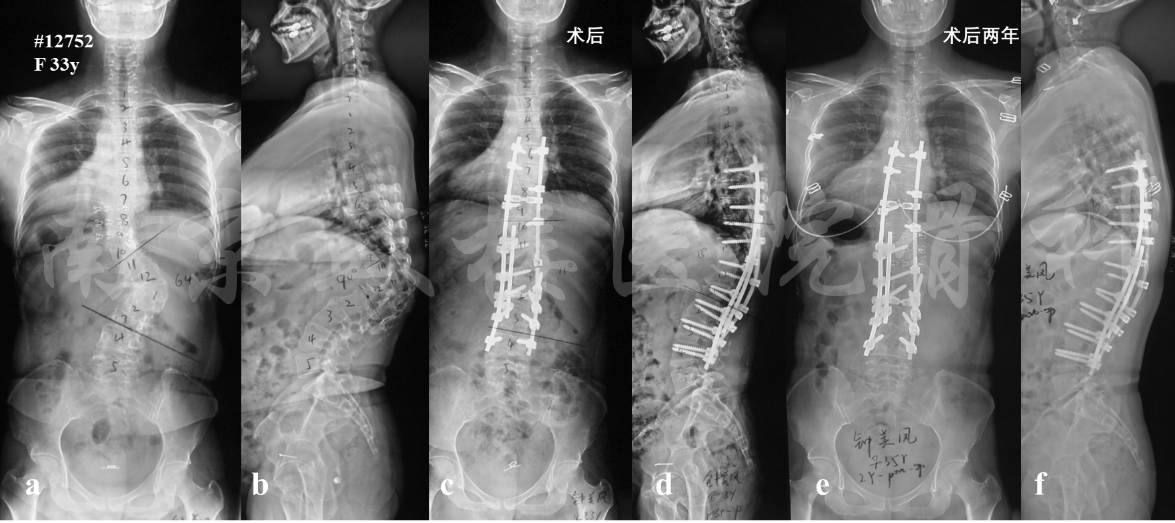

图3 女,41岁,术前X片示侧凸及后凸顶椎均为L1(a, b),因此行L1 PSO截骨术, 前路钛网支撑融合(c),术后1年截骨区假关节形成,出现双棒断裂,钛网倾斜(d),遂行前后路联合翻修术,翻修术后6年无内固定失败(e, f)

图5 女性,33岁,成人先天性脊柱侧后凸畸形。X片示T12楔形变,胸腰段角状侧后凸畸形(a, b),行T12全脊椎切除术(T12 VCR),并于截骨区使用卫星棒加固(c, d),术后两年无内固定失败或矫正丢失(e, f)